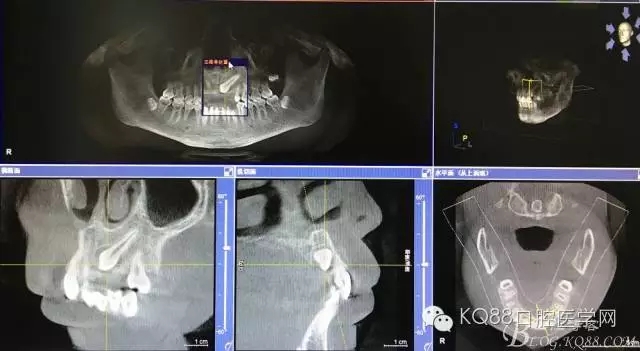

圖1.術(shù)前的cbct影像檢查:23位于腭側(cè)、牙齒位置比較高。